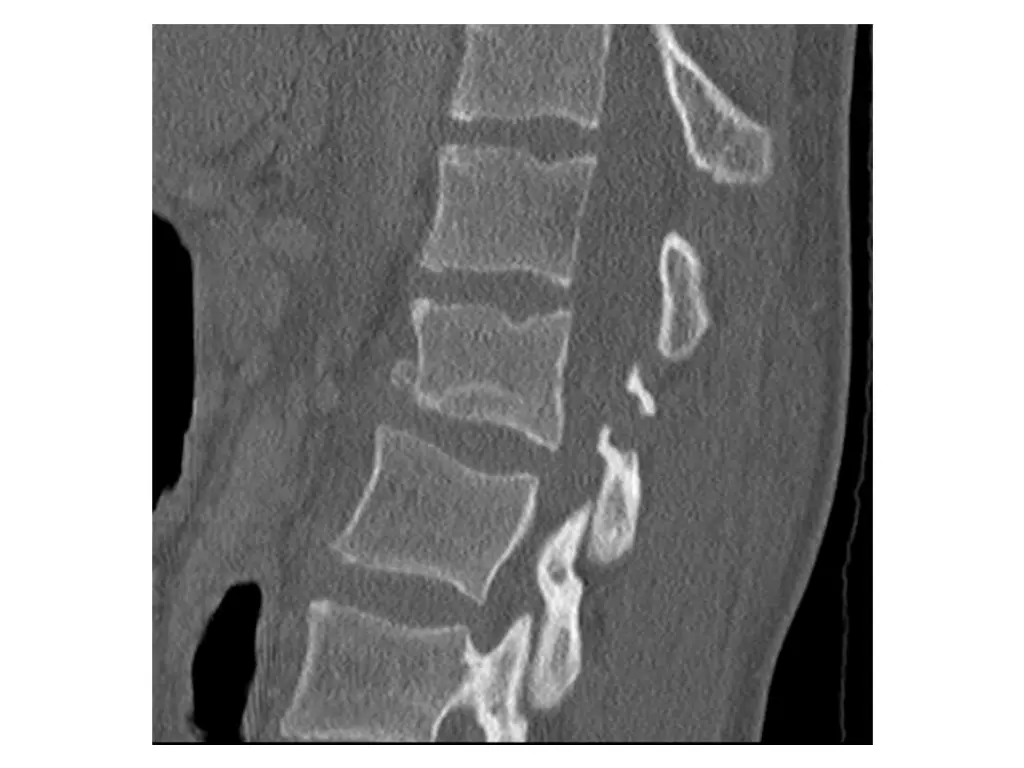

Clinical Hx (Case 2) 30 year old male. Fell approximately 30 feet landing on back. Immediate complaints of back pain. Transported to FMC. Hemodynamically stable. No LoC. Isolated injury to thoracic or lumbar spine.

Neurological exam (Case 2) Upper extremity: Sensory: Normal to light touch and pinprick Motor: 5/5 power in all muscle groups Lower extremity: Sensory: L3-S2 left sided numbness, otherwise normal to light touch and pinprick Motor: 5/5 power in all muscle groups Rectal: Sensation: Normal to light touch and pinprick Voluntary sphincter tone: Normal Other relevant findings: None

Imaging (Case 2) Lateral XR Midsagittal CT scan Parasagittal CT scan Axial CT scan